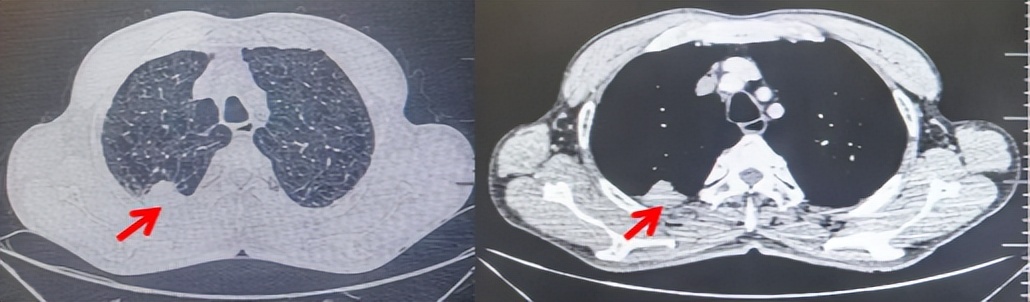

71岁男性,高血压病史20年,口服药物治疗,无糖尿病、心脏病等基础疾病,吸烟史50年,20支/天,已戒1年余,无饮酒史,无肿瘤家族史。2023.11因咳嗽、咳痰行胸CT检查:左肺下叶占位性病变,大小约12mmx8mm(如图5)。2023.11.20行“单孔胸腔镜左肺中下叶切除、肺门及纵隔淋巴结清扫、胸膜粘连松解术”;术后病理:(左肺下叶)结合免疫组化鳞状细胞癌(中、低分化),局部见脉管内癌栓,未见确切神经侵犯,(气管切缘)净。(淋巴结)未见转移癌0/19(4组0/1;5组0/1;6组0/2;7组0/1;9组0/1;10组0/2;11组0/3;12组0/2;13组0/2;14组0/4)。术后分期pT1bN0M0 IA期,术后定期复查。

图5:患者手术前(2023.11)胸部CT肺窗及纵隔窗

图6:患者胸膜及纵隔转移(2024.09)胸部CT肺窗及纵隔窗

图7:替雷利珠单抗联合白蛋白紫杉醇+卡铂治疗4周期后(2024.12)胸部CT肺窗及纵隔窗